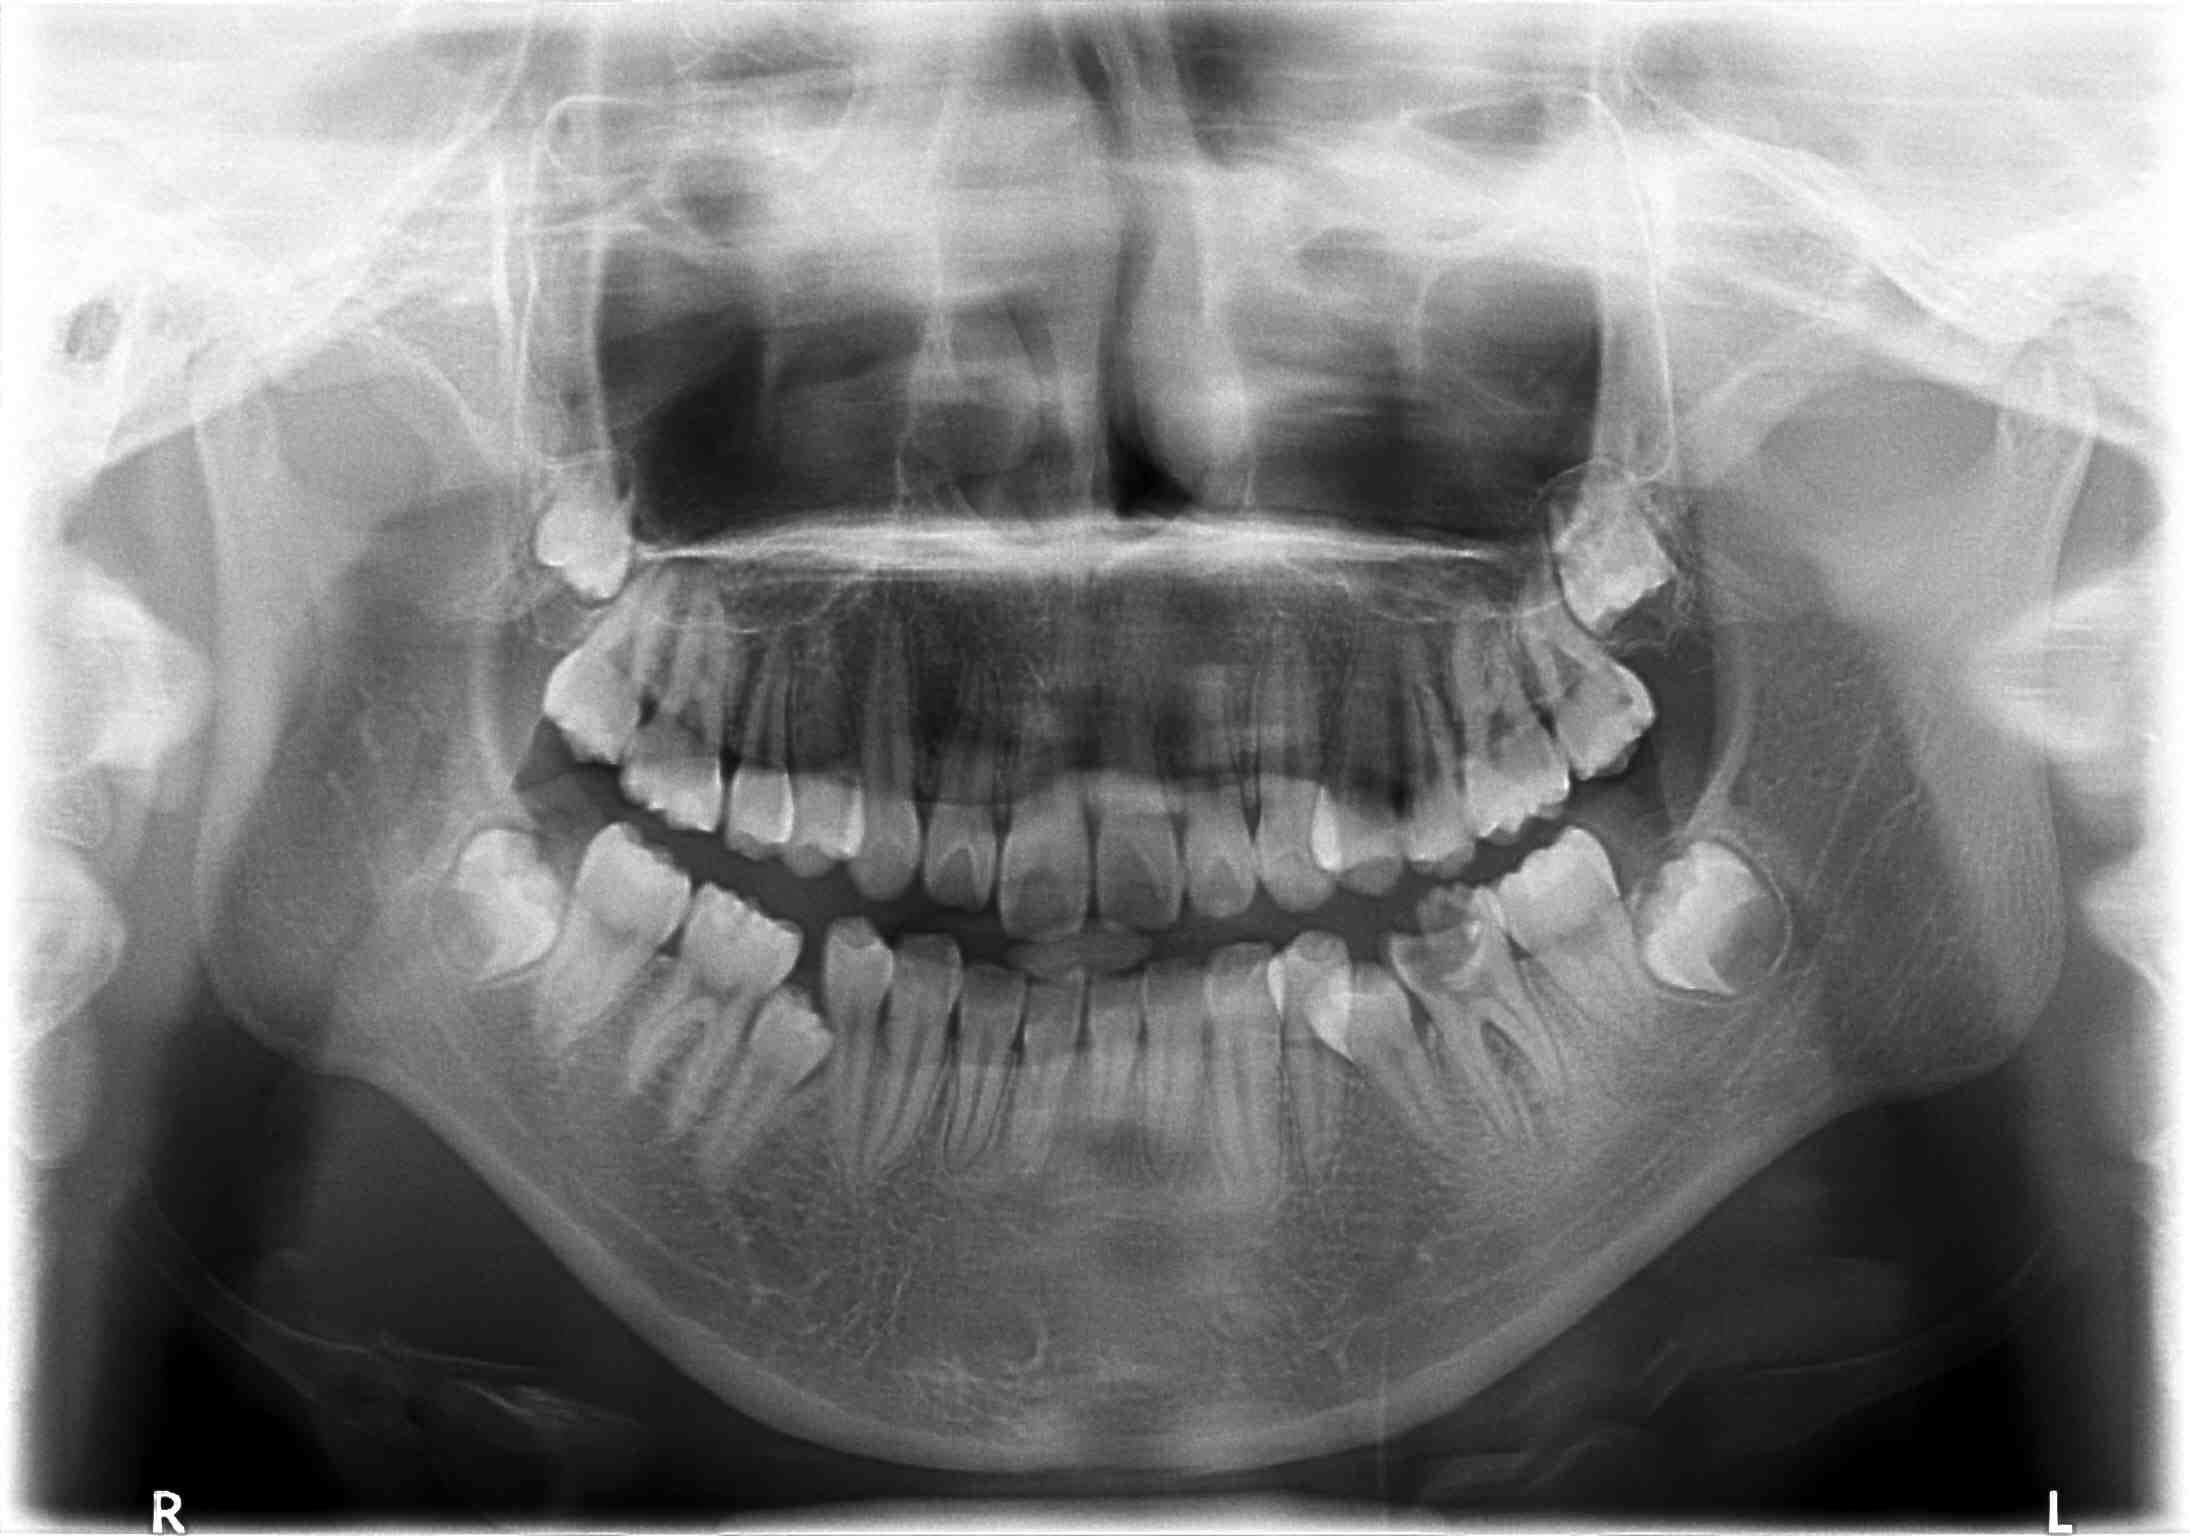

生活中,经常会有人因为牙齿缺损而烦恼,一般牙齿缺损的常见原因有:龋齿、牙齿脱落、重度氟斑牙以及意外等造成的。牙齿缺损严重影响形象。所以患者会及时修复。在修复方法选择上基本就是瓷贴面、美牙冠、烤瓷牙等等。那么牙齿修复价格是怎么计算的呢?

康贝佳口腔表示,关于牙齿修复价格方面的因素,有很多不确定因素,比如缺损程度、选择的修复方式等等。具体有以下几个原因: